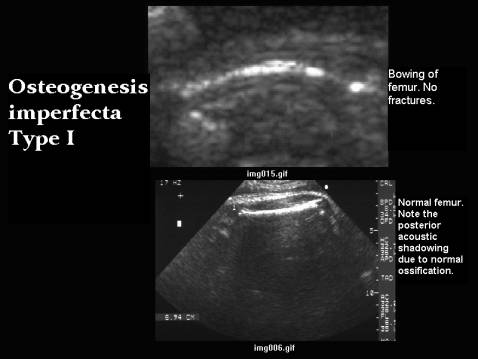

I

Mild bowing of long bones.

No fractures.

No IUGR.